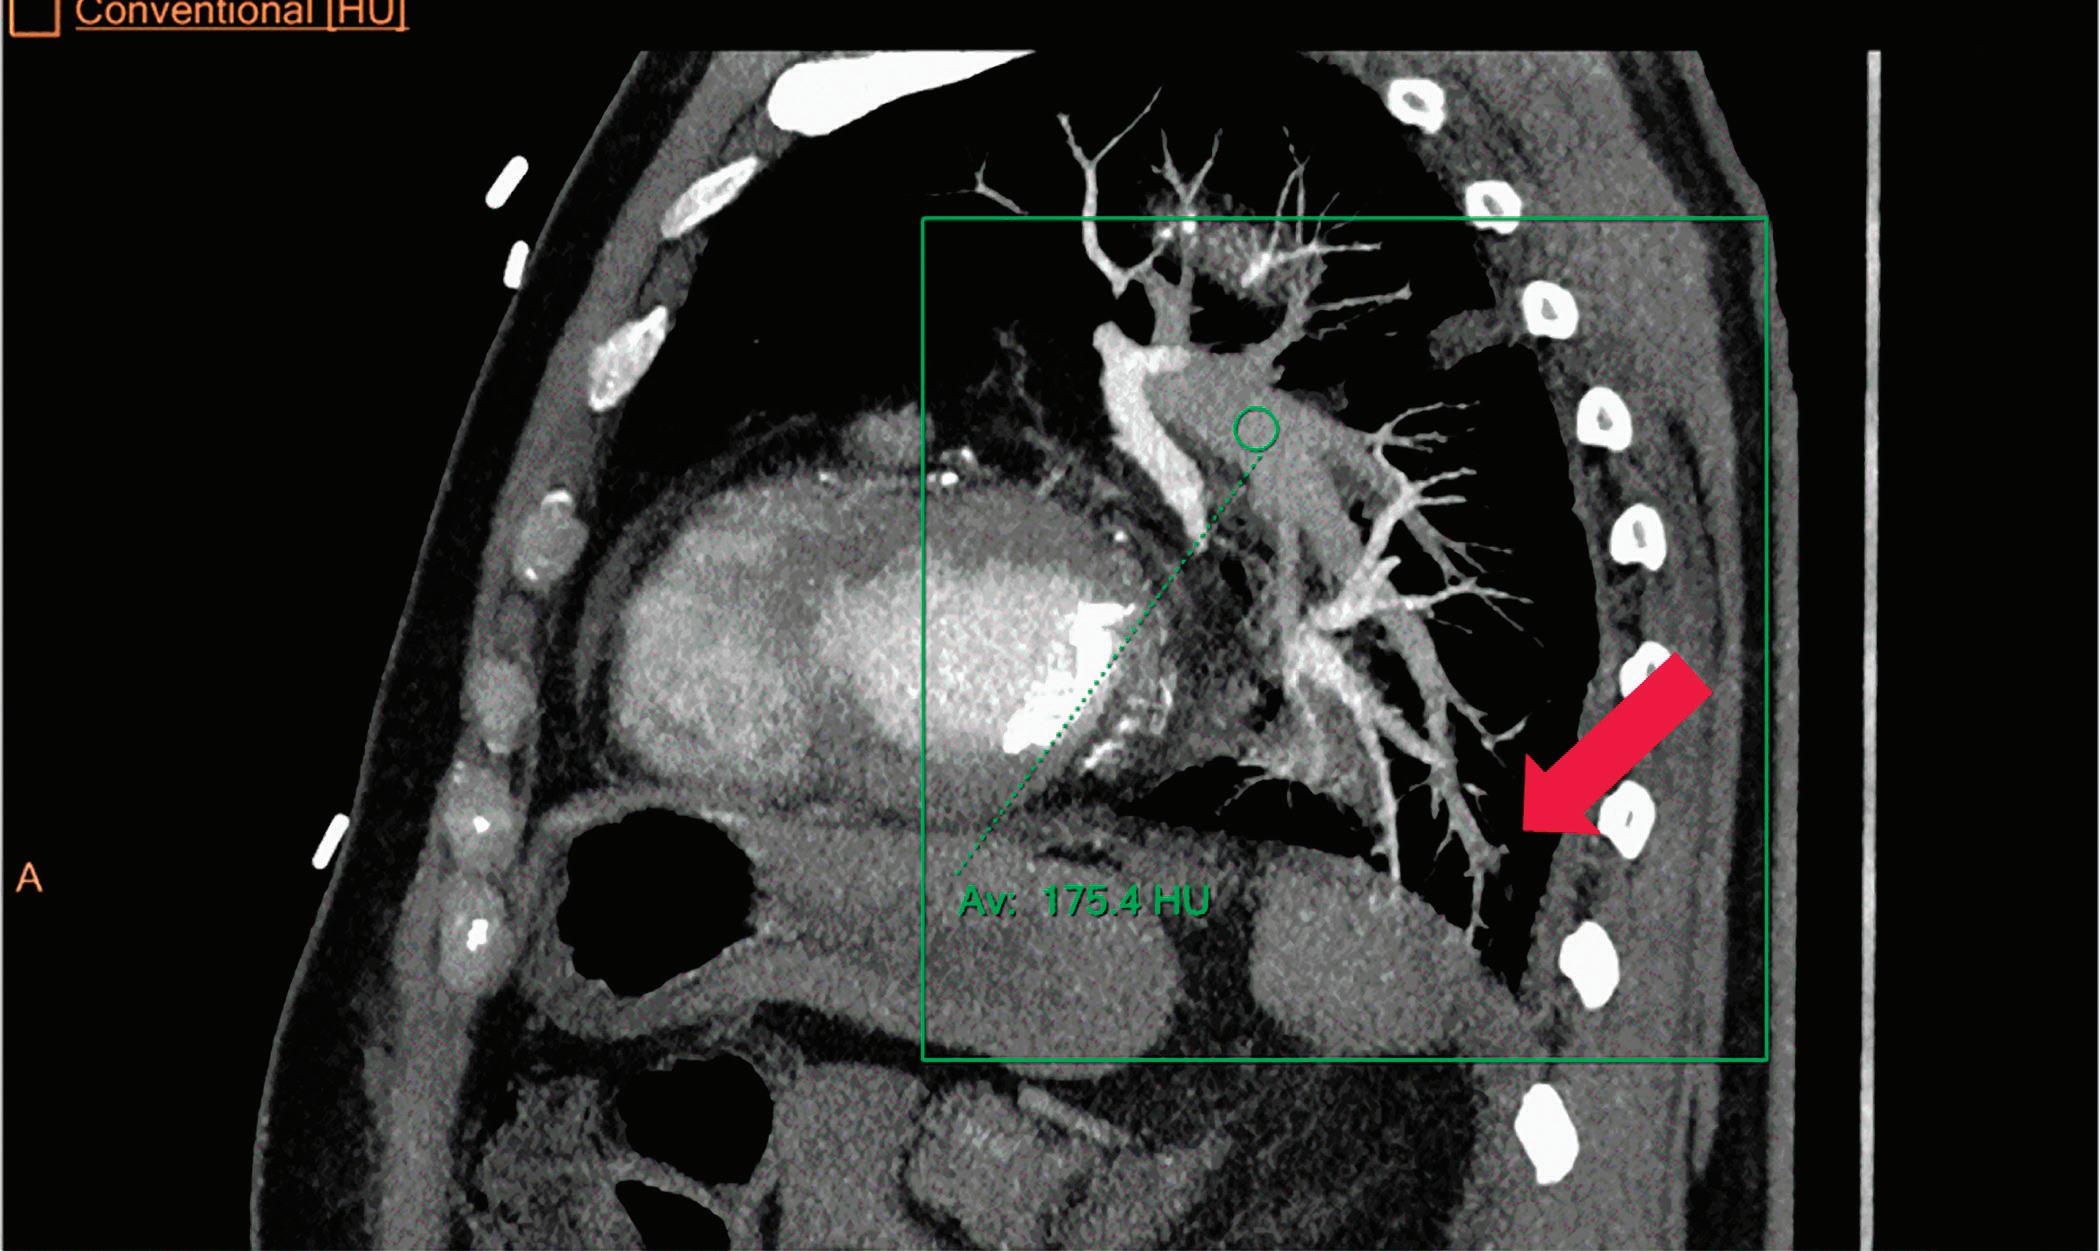

CT breath-hold results in a poor enhancement of the pulmonary arteries on the displays from left to right: monoenergetic 70 keV, monoenergetic 55 keV, monoenergetic 40 keV, and Z effective map showing a perfusion deficit of the lung parenchyma (white arrow). When decreasing the energy, the iodine attenuation is progressively boosted and reveals the presence of a thrombus (colored arrows) in a sub-segmental pulmonary artery corresponding to the territory of the perfusion deficit. (c) Monoenergetic 200 keV reduces beam hardening from dense contrast medium compared to conventional CT images.

Once the pair (αp, αc) is calculated for every voxel, and since fp(E) and fc(E) are known functions of energy, one may synthesize monochromatic images at different energies. These images can be used for routine diagnosis similar to conventional images. With a single scan at 120 kVp (or 140 kVp for obese patients), a dual-layer spectral CT acquisition allows the reconstruction of virtual monochromatic images from 40 keV up to 200 keV, in increments of 1 keV. The minimum of 40 keV was chosen in order to stay above the k-edge of the most common materials including iodine (iodine k-edge = 33 keV). If the scan is performed at 120 kVp, the conventional CT images of a typical-size patient will display an attenuation corresponding to the average of the X-ray spectrum (˜70 keV in a body scan) but with beam hardening artifacts from dense structures (like bones) which are due to the polychromatic nature of the X-ray beam. Since the photoelectric effect is dominant at lower keV, and is relatively high for high Z materials, low keV imaging (below 70 keV for body) can be used to enhance the absorption of high Z material such as iodine (Z=53), compared to the conventional CT images.15,16 This can be of particular interest to enhance the iodine uptake for patients with renal dysfunction, where the total injected volume of iodinated contrast medium is very limited. This attenuation boost can also be very useful in the case of a missed injection (Figure 2a and b). Compton scattering on the other hand is dominant at higher keVs and does not exhibit a strong relationship with Z. High keV imaging will then be of particular interest to minimize the absorption of high Z materials and minimize all types of associated artifacts (metal beam hardening from metal implants, beam hardening from dense contrast medium, blooming of stents or calcium, etc.) (Figure 2c).17,18,19

Virtual monoenergetic images obtained from the IQon Spectral CT scanner have low noise across the entire spectrum of energies,20 and this noise is lower than in conventional images due to the spectral reconstruction processing that includes noise suppression algorithms that make use of the additional spectral information. This provides significant SNR and CNR improvements compared to conventional polyenergetic images. The low noise of monoenergetic images at various energy levels makes them usable at all energy levels, particularly at low energies for enhancing vascular contrast or improving lesion conspicuity and at higher energies for decreasing artifacts.